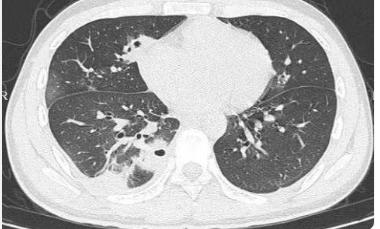

刷到20岁男生肺被查出10多个空洞的新闻,我直接惊掉下巴!本该是跑跳都带风的年纪,肺部却藏着这么多隐患,这事儿真的给所有年轻人敲了记响钟! 说实话,现在好多人都有个误区:觉得年轻就是免病金牌,熬夜打游戏、抽烟解压、感冒咳嗽硬扛,怎么造都行。但我身边就有例子,朋友仗着20出头,天天凌晨两三点睡,还爱抽电子烟,前段时间体检查出肺结节,吓得立马戒了所有坏习惯。 这事儿真不是危言耸听!肺部其实特别娇弱,长期熬夜会让免疫力下降,烟草(包括二手烟、三手烟)更是直接伤肺,就连密闭空间不通风、长期待在空调房,都在悄悄损伤肺功能。很多人觉得咳嗽、胸闷是小毛病,殊不知这些可能就是身体的求救信号,拖来拖去只会让小问题变大事。 其实守护肺部健康真没那么复杂:别仗着年轻瞎造,尽量11点前睡,戒烟并远离吸烟环境;每天抽20分钟做个慢跑、跳绳,让肺动起来;每年体检别偷懒,胸部CT真的能早发现问题;要是咳嗽超过两周、痰里带血,别硬扛,赶紧去医院! 年轻是资本,但不是挥霍健康的理由。我们追求的是长久的快乐,而不是一时放纵后的后悔。好好爱护自己的肺,才能一直畅快呼吸、奔赴热爱呀!